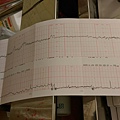

5週1天

6週1天

7週2天

8週5天

9週5天

10週6天

12週5天-1

12週5天-2

16週5天

20週5天(臉部)

23週1天-高層次超音波(女生)

20週5天

24週6天

28週6天

30週2天

31週1天

32週5天(臉部)

32週5天

34週5天-2

36週6天-2

37週5天(臉部)

37週5天-1